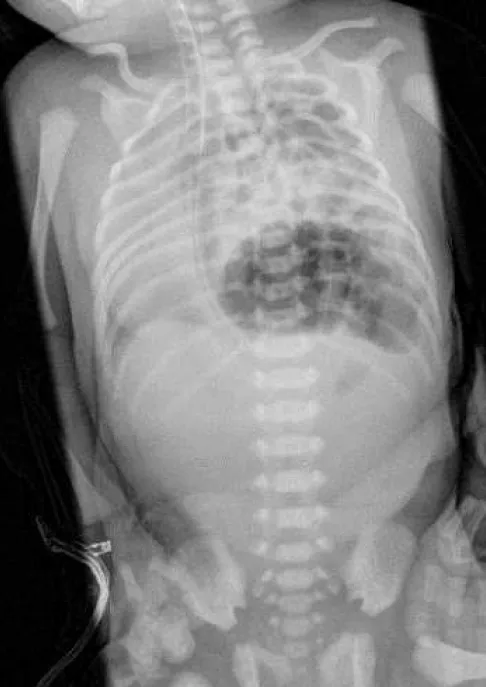

新生兒出生後即有呼吸窘迫、心音移位,且胸部X光片顯示胸腔內有腸道氣體影,這些都是典型的先天性橫膈膜疝氣表現。